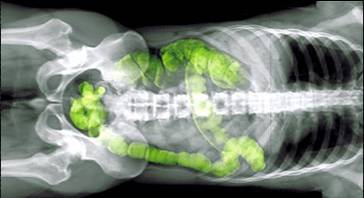

"100 Millionen Nervenzellen umhüllen den menschlichen Verdauungstrakt; hier die eingefärbte Röntgenaufnahme eines Dickdarms